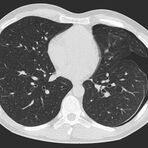

Thorax (Brustkorb)

• Entzündungen oder Tumore des Mediastinums und der Lunge

• Lungenembolie- Diagnostik

• hochauflösende Darstellung des Lungenparenchyms zur Abklärung chronischer interstitieller Erkrankungen wie z. B. Fibrosen, Emphysem, Bronchiektasen

Die Zeitspanne für die Untersuchung hängt von der Größe des Untersuchungsbereiches ab. Einzelne Untersuchungen dauern nur wenige Sekunden (die der Lunge z. Bsp. ca. 7 bis 12 Sekunden). Einschließlich Lagerung auf der Untersuchungsliege und der Planung der Untersuchungsbereiche ist eine solche Untersuchung insgesamt meist nach 5 bis 10 Minuten beendet.